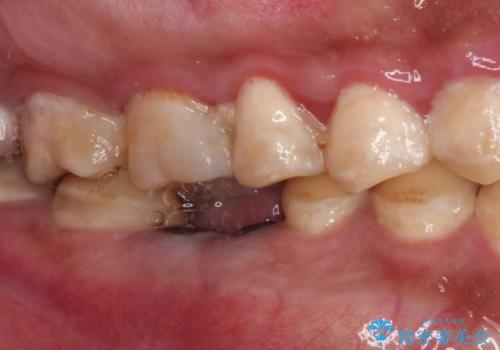

- 奥歯が痛く、放置した虫歯があるとのことで来院された患者様です。

全体的に汚れが多く、歯の表面の脱灰が全体的に認められましたが、まずは奥歯の虫歯治療から行うこととしました。

根っこだけとなっている歯は抜歯をし、奥の大きな虫歯となっている歯は、神経を取り除く可能性を考慮しながら処置を進めて行くこととしました。